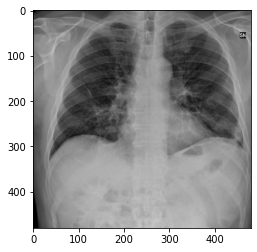

img = img[np.newaxis,:,:,:]This is the image we want the COVID-Net model to analyze:

Now everything is ready to be sent to the Confidential AI server: